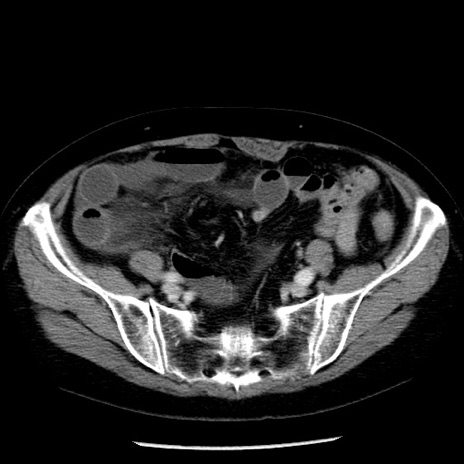

症例13(横断像)

【症例】70歳代女性

【主訴】腹痛、嘔吐

【現病歴】15時間程前(昨晩)より腹痛あり。今朝になっても症状の改善なく、嘔吐あり。腹痛も増悪あり、救急外来受診。

【既往歴】子宮癌全摘術後

【身体所見】意識清明、BP 121/72mmHg、P 74bpm、SpO2 100%(RA)、腹部:平坦・軟、腸雑音ほぼ聴取せず。下腹部・心窩部・臍左上に圧痛あり。反跳痛なし。

【データ】WBC 10600、CRP 0.15